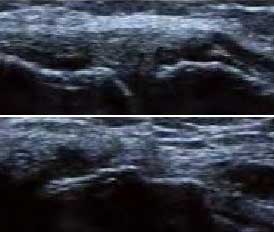

3、准确判断关节积液增加,精准判定RA严重程度

类风湿关节滑膜炎症会导致滑液渗出不断增多,形成关节腔积液。肌骨超声最少可发现1ml的积液,能对关节腔积液量及位置准确定位,通过检测判定关节腔内液性边界清楚的无回声区、细点状回声或细微的低回声条纹,判断其宽度和深度衡量积液量的多少,进而评估RA的严重程度。

Ⅰ级微量积液

滑膜囊内见前后径3.55mm液性暗区,呈椭圆形

Ⅱ级较多量积液

暗区内有团状高回声,可见深度达6.46mm液性暗区

Ⅲ级大量积液

关节囊扩张,可见大范围液性暗区,髌上囊积液深度达11.2mm